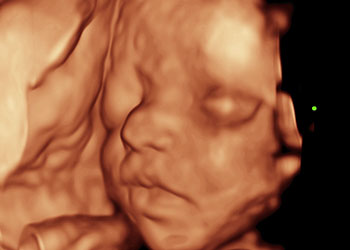

Ejemplos de ecografías del embarazo